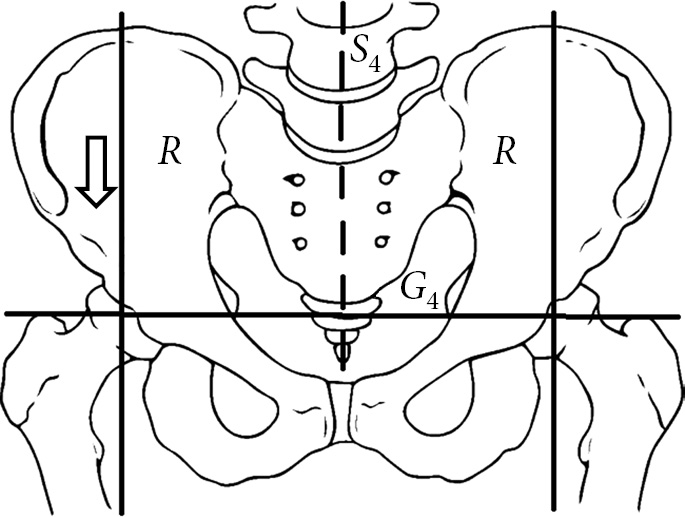

When a healthy person stands on two legs, the weight of their body bears on the hip joints. The human pelvis rests on the heads of the hips. In a vertical position, the center of gravity of the body, which includes the partial bodyweight of G4 (head, body, two arms), is directed vertically in the frontal plane (Fig. 1).

Fig. 1. Schematic representation of the load on the hip joints when a person is standing on both limbs (according to Pouwels)

Bodyweight of G4 is concentrated in S4 and is evenly distributed on both heads of the hips. Thus, each hip joint holds half the body weight of G4, and the resulting R is directed vertically downward.